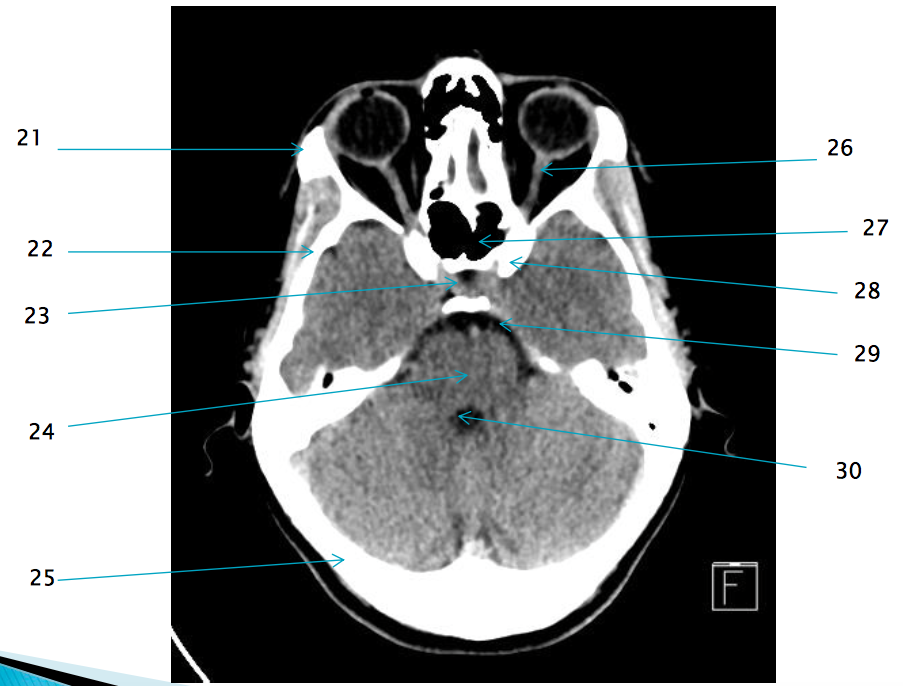

21

22

R temporal bone

29

Pre pontine cistern

28

L anterior clinoid process